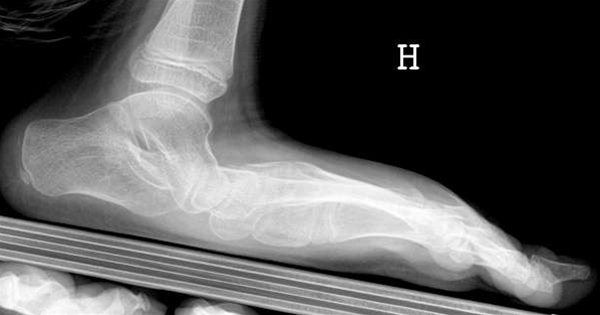

Røntgen af platfod

Det er normalt ikke nødvendigt med røntgenundersøgelse. Men det kan nogle gange være nyttigt for at udelukke andre sygdomme.